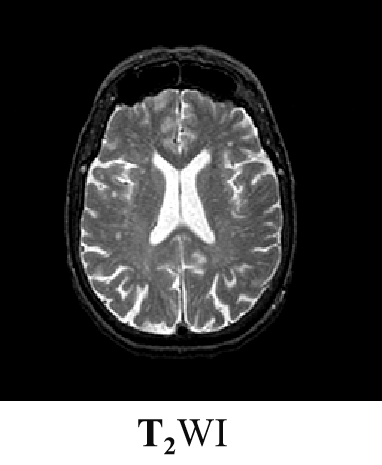

磁共振成像(Magnetic Resonance Imaging , MRI)是利用原子核在强磁场内发生核磁共振产生的信号经图像重建的成像技术。

磁共振成像过程中,射频脉冲激发后所记录到的信号强度的大小主要与以下因素有关:

一是生物组织本身的因素,包括T1、T2和质子密度等;

二是脉冲序列的形式。

T2加权:

PD加权: